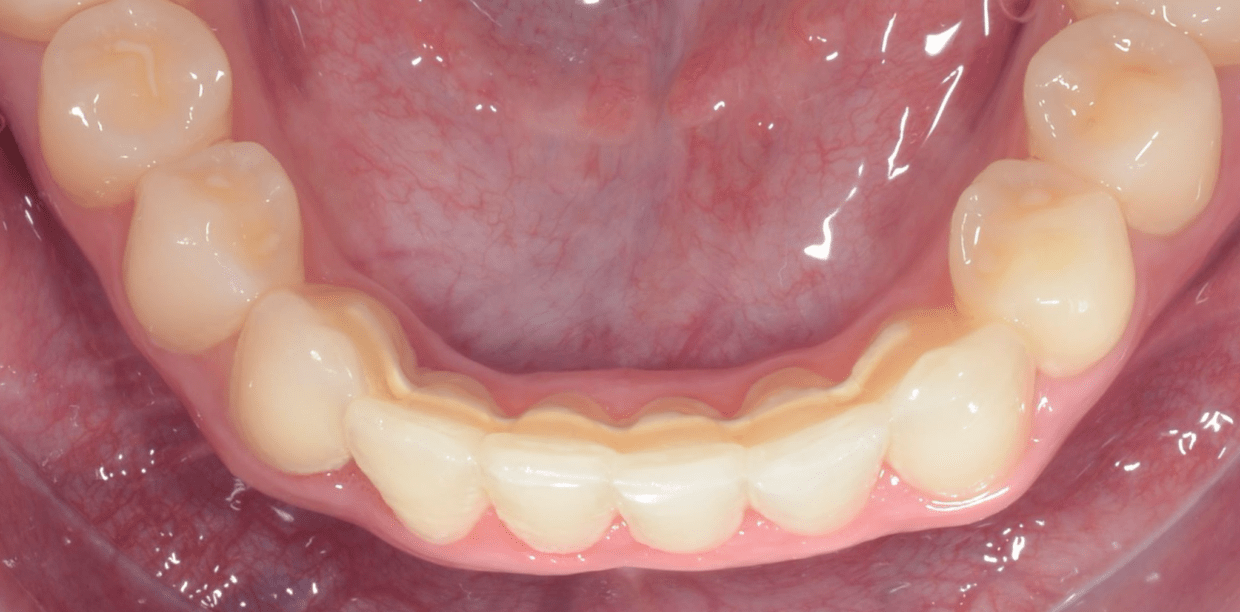

Simple - A2

Simple - A2

Simple - A2

Simple - A2

Simple - A2

Simple - A2

Simple - A2

Simple - A2